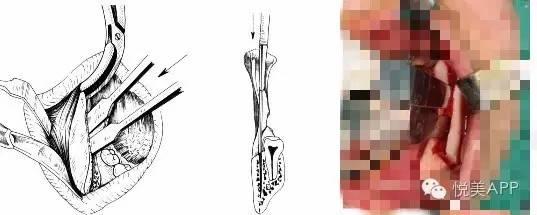

悦大咖放一个下颌支矢状骨劈开术,大家不要害怕(看懂示意图就可以了)~

切开与显露

矢状与垂直骨切开

劈开下颌支

从矢状面劈开下颌支

移动远心骨段之后~固定

固定

检查咬合并固定